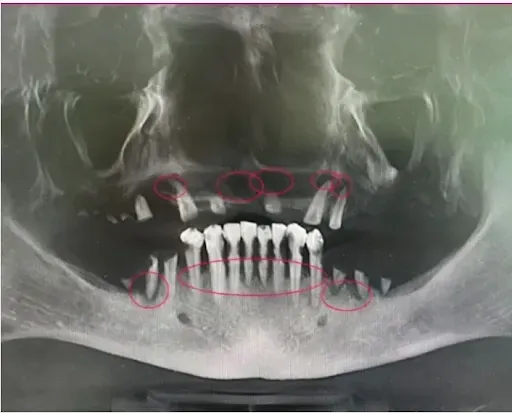

❌ Missing 1-2 teeth: Significant bone loss in 6-12 months

❌ Multiple missing teeth: Accelerated deterioration

❌ Infection present: Bone becomes "too soft to build on"

❌ Point of no return: Ineligible for implants permanently

✅ All infected teeth removed → eliminates source of infection

✅ Bone thoroughly cleaned → removes all infection

✅ Implants placed immediately → stimulates bone like natural roots

✅ Permanent teeth attached → full function restored